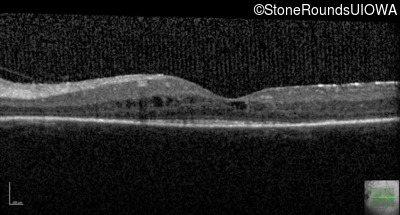

Visit at age: 16 years

Optical Coherence Tomography - Right - 20/30 -2

Exemplar / OCT Stack